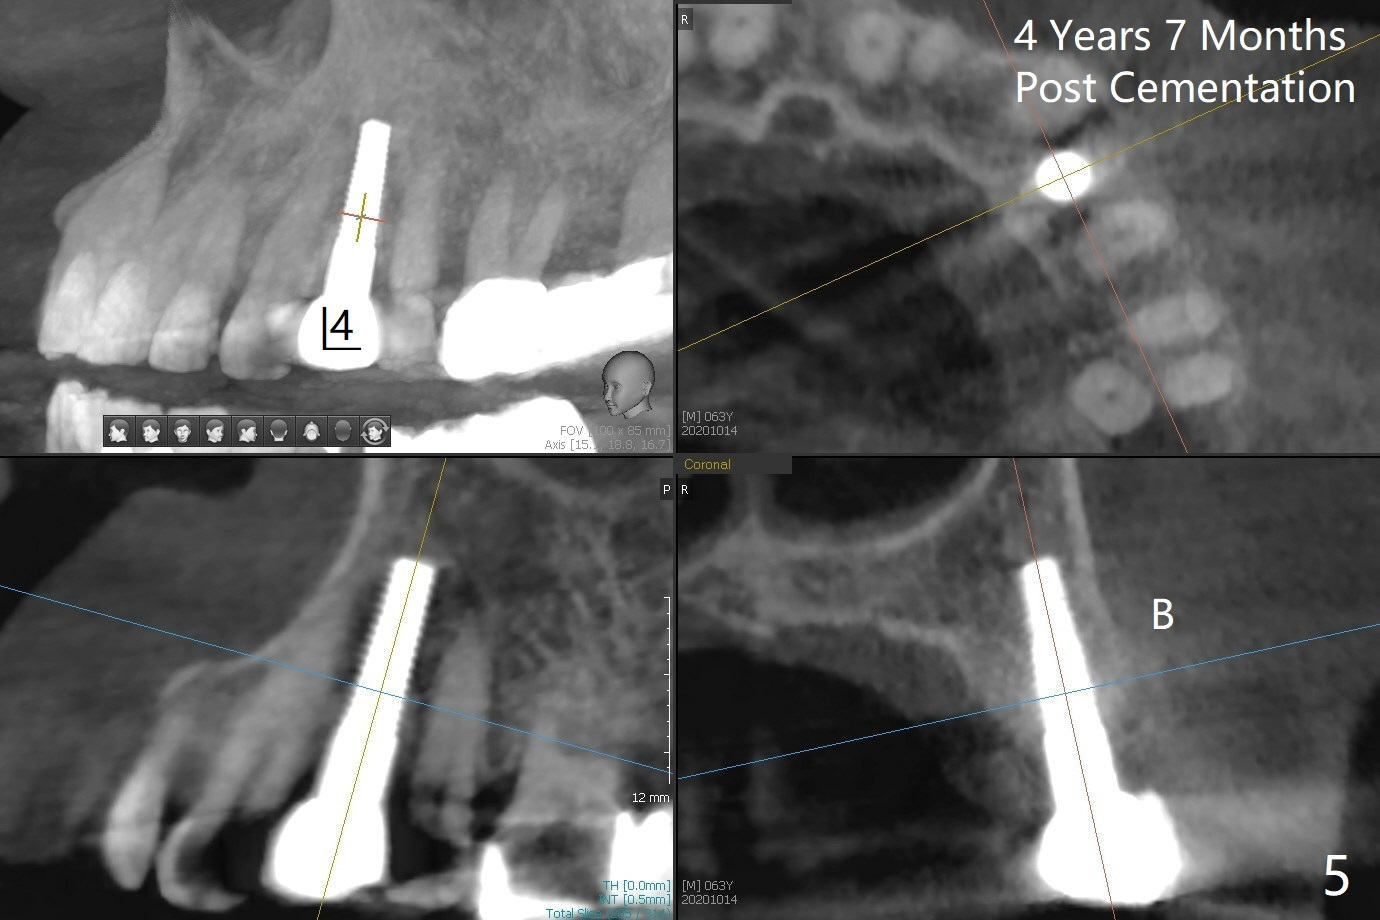

63岁女右上6远中龋齿在邻牙植牙牙冠粘固后2年8个月坏的严重(图一),病人决定拔除种植。之前嘱咐她回来修复,部分由于新冠病毒,她拖延治疗。今后需要建立一个植牙后完整随访和严密检查系统,减少继发龋。分析四个植牙(图二,四至六)表明骨质宽度优越,右上6即刻种植应该没问题(图三)。植体选择与邻近一致。Prevent Molar Periimplantitis (Protocols, Table) No Neighboring Caries Metronidazole Magicore Cases 手术 2 Xin Wei, DDS, PhD, MS 1st edition 10/14/2020, last revision 11/17/2020